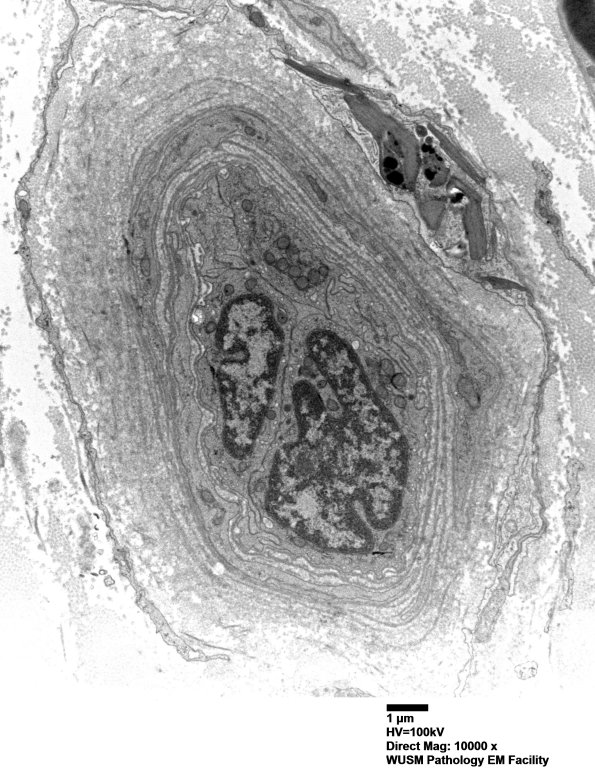

Washington University Experience | VASCULAR | Hypoxia-Ischemia, fetal-neonatal | White Matter | 16B5 (Case 16) HIEM EM028 - Copy

16B5 (Case 16) HIEM EM028 - Copy